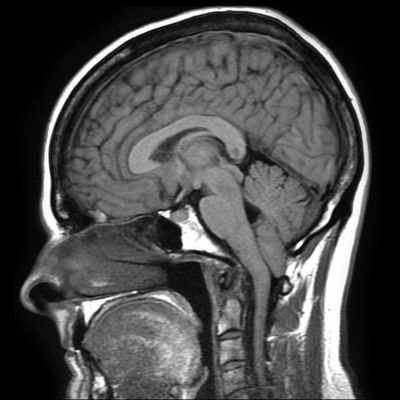

МРТ головного пациента с ААК I типа – смещение миндалин мозжечка в позвоночный канал

ниже уровня большого затылочного отверстия (более 6 мм)